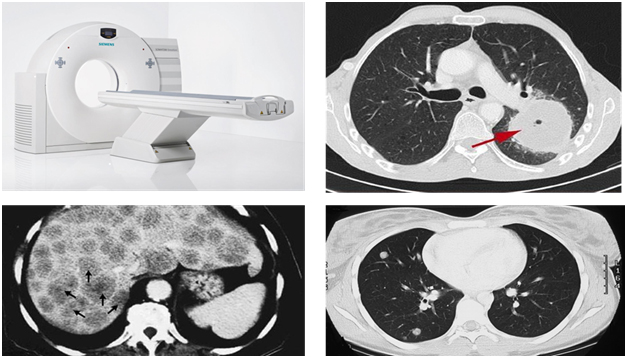

Компьютерная томография

Компьютерная томография нередко используется для визуализации не полых, т.е. паренхиматозных органов. На картинке ниже (снимках компьютерной томографии) вы можете увидеть крупное первичное образование лёгкого, вторичное метастатическое поражение печени.